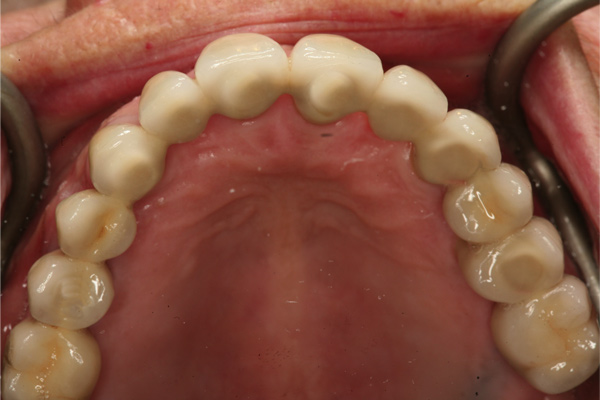

Fig 12. Frontal view (Fig 12) and occlusal view (Fig 13) of clinical application of dual-axis principles. (Images courtesy of Costa Nicolopoulos, BDS)

Figure 12

Fig 13. Frontal view (Fig 12) and occlusal view (Fig 13) of clinical application of dual-axis principles. (Images courtesy of Costa Nicolopoulos, BDS)

Figure 13

With the increased application of this concept, more options have been introduced, including 24-degree and 36-degree correction (Figure 11 through Figure 13). At present, larger angular corrections are available with external hexagon connection systems, while the 12-degree connection is also available in most internal connection configurations.

Fig 11. Panorex of clinical application of dual-axis principles. From left to right: 36-degree tooth No. 4; 24-degree tooth No. 6; 12-degree tooth No. 8; 12-degree tooth No. 9; 24-degree tooth No. 11; and 36-degree tooth No. 13. Angulation is designed to avoid maxillary sinus and buccal constraints of the anterior maxilla. (Image courtesy of Costa Nicolopoulos, BDS, Dubai, United Arab Emirates)

Figure 11